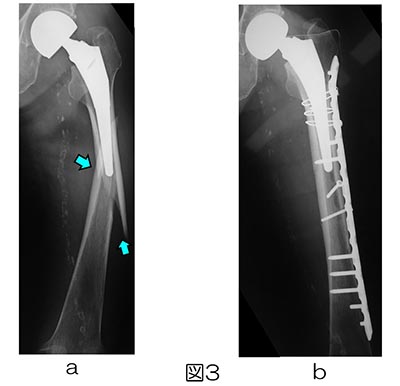

「インプラント周囲骨折を極める」馬場智規定価: ¥ 15000#馬場智規 #本 #自然/医療・薬学・健康裁断済みです。書き込みなどはありません。| カテゴリー: | 本・雑誌・漫画>>>本>>>健康・医学 |